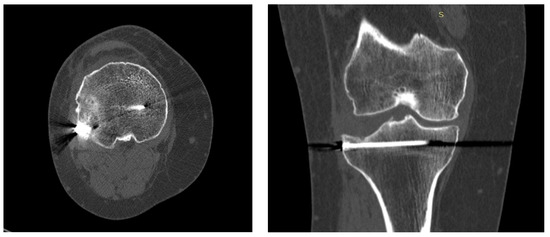

2. Clinical Case Presentation